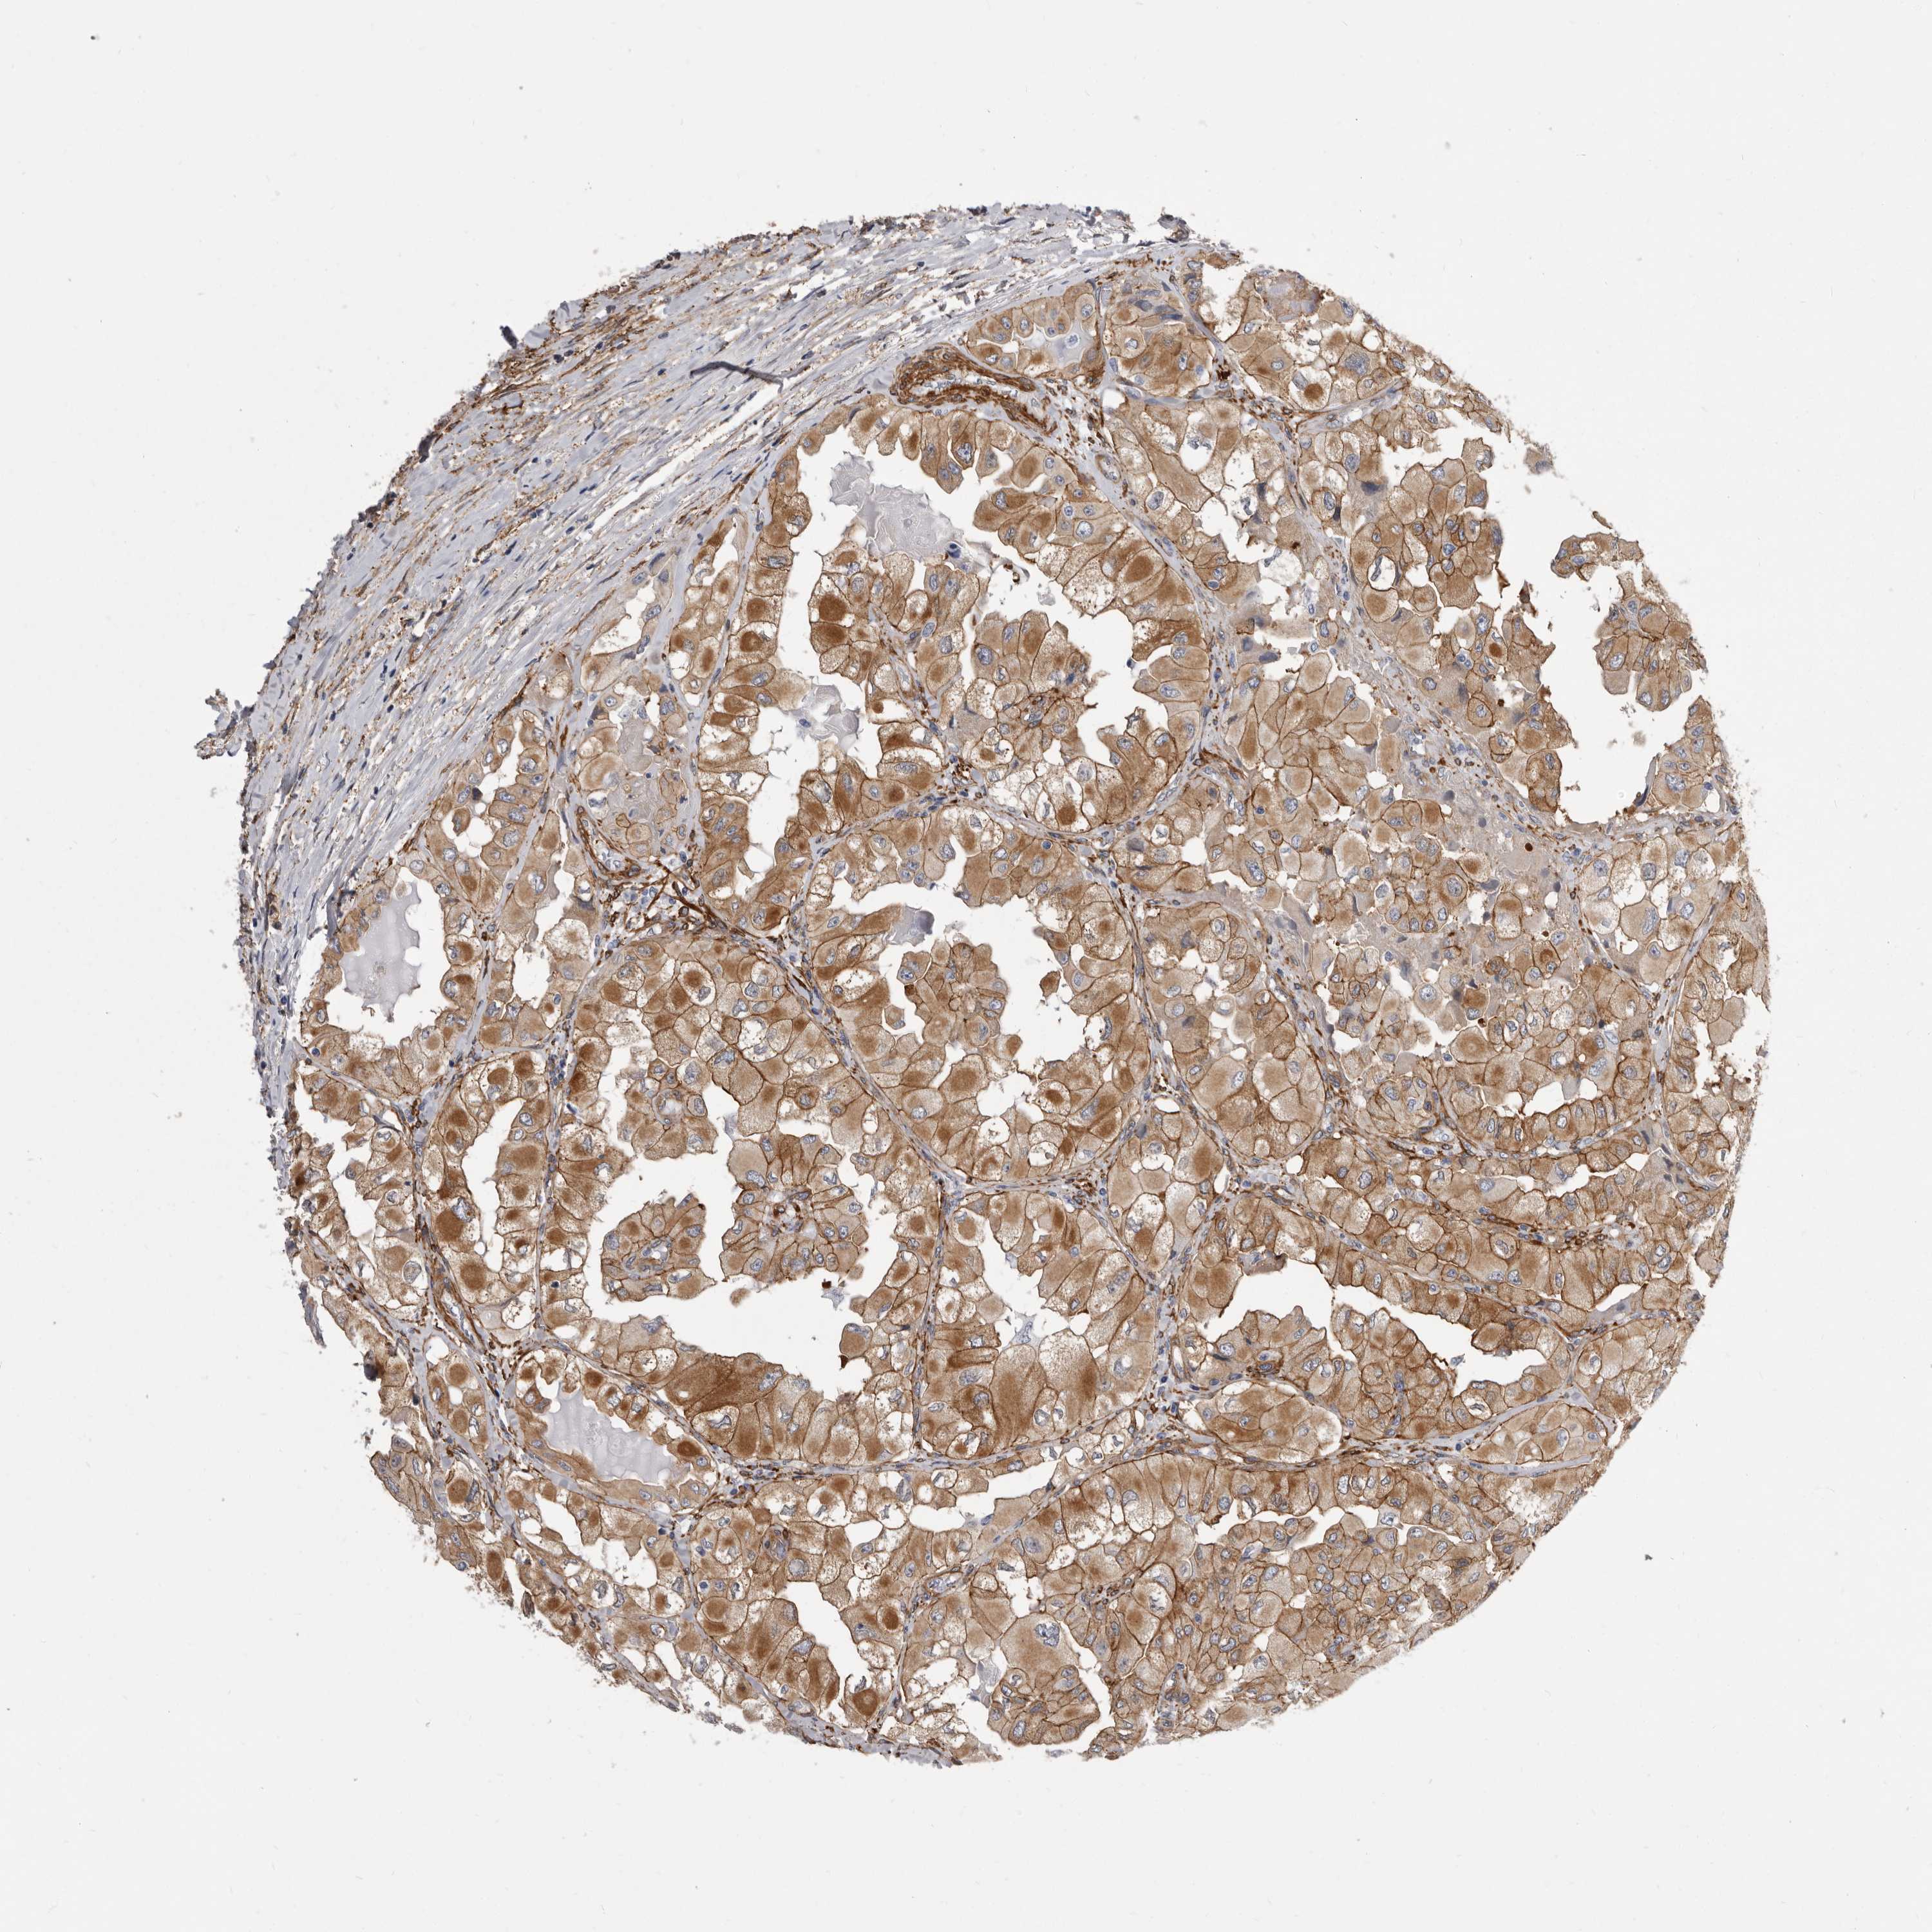

THYROID CANCER - Protein expressioni

A mouse-over function shows sample information and annotation data. Click on an image to view it in a full screen mode. Samples can be filtered based on level of antibody staining by selecting one or several of the following categories: high, medium, low and not detected. The assay and annotation is described here.

Note that samples used for immunohistochemistry by the Human Protein Atlas do not correspond to samples in the TCGA dataset.

Antibody stainingi

Antibody staining in the annotated cell types in the current human tissue is reported as not detected, low, medium, or high, based on conventional immunohistochemistry profiling in selected tissues. This score is based on the combination of the staining intensity and fraction of stained cells.

Each image is clickable and will lead to virtual microscopy that enables deeper exploration of all samples and also displays staining intensity scores, fraction scores and subcellular localization as well as patient and tissue information for each sample.

Antibody HPA028448

Antibody HPA028696

Staining

High

Medium

Low

Not detected

Intensity

Strong

Moderate

Weak

Negative

Quantity

>75%

75%-25%

<25%

None

Location

Nuclear

Cytoplasmic/membranous

Cytoplasmic/membranous,nuclear

Papillary adenocarcinoma, NOS

Follicular adenoma carcinoma, NOS